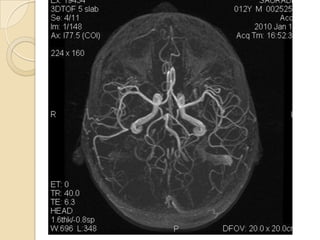

Arteries of the brain (cranial view) - MRA

1. Anterior cerebral artery

2. Anterior communicating artery

3. Basilar artery

4. branches (in insula) of middle

cerebral artery

5. Cavernous portion of internal

carotid artery

6. Cervical portion of internal carotid

artery

7. Genu of middle cerebral artery

8. Intracranial (supraclinoid) internal

9. Middle cerebral artery

10. Ophthalmic artery

11. Petrous portion of internal carotid

12. Posterior cerebral artery

13. Posterior cerebral artery in ambient

cistern

14. posterior cerebral artery in

interpeduncular cistern

15. Posterior communicating artery

16. Posterior inf cerebellar artery.

17. Quadrigeminal portion of posterior

18. Superior cerebellar artery

19. Vertebral artery